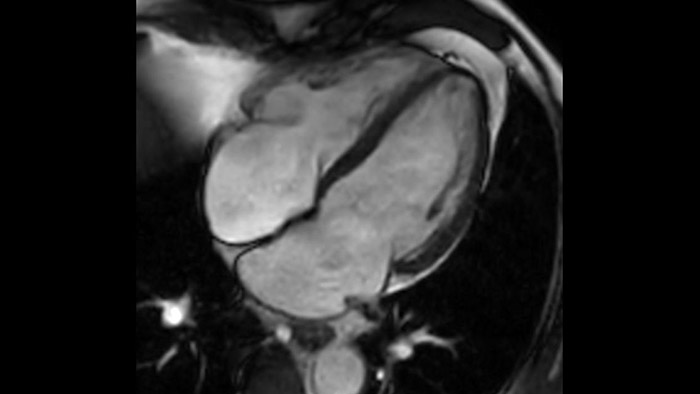

Today's diagnostics often cannot detect heart dysfunction until symptoms occur. MyoStrain utilises segmental strain to measure 48 segments of the heart and provides physicians with a unique diagnostic tool to help identify regional dysfunction before the heart as a whole is affected.

Diagnostic and prognostic utility of cardiac MR is increasing. Assess the anatomy and function of the heart using cine acquisitions, acquire information about perfusion and viability of the cardiac tissue, visualise potential edema with black blood sequence, access and even quantify tissue characterisation with CardiacQuant.

IntelliSpace Portal MR Caas5,6 Strain7 assists in patient diagnosis and monitoring by providing global strain parameters such as global longitudinal strain (GLS), global circumferential strain (GCS), and global radial strain (GRS), using short and long axis MR images, as well as describing the myocardium deformation- such as shortening, thickening, and lengthening during the cardiac cycle.